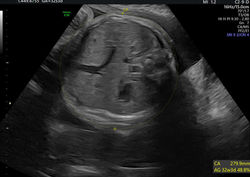

Toutes les échographies de première intention peuvent être réalisées au cabinet: datation, premier, second et troisième trimestre.

Mais aussi les échographies gémellaires, surveillance de croissance et doppler maternel et foetal, mesure du col.